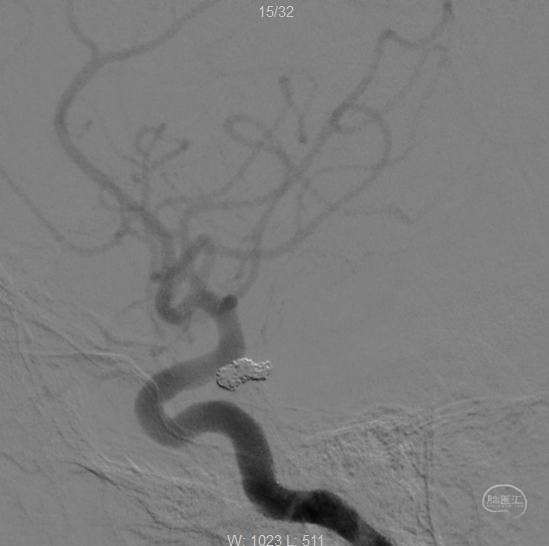

两根微导管到位(箭头示微导管2),先经过微导管1植入一枚,三维Target3-4弹簧圈,不解脱。

再经过微导管2植入一枚,三维Target2-6弹簧圈。

再经过微导管2,植入一枚二维target2-4弹簧圈。